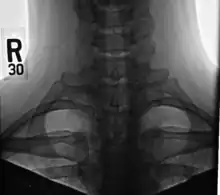

3D CT reconstruction of a cervical rib.

Bilateral, symmetric, full, ossified cervical ribs.

On imaging, cervical ribs can be distinguished because their transverse processes are directed inferolaterally, whereas those of the adjacent thoracic spine are directed anterolaterally.[11]